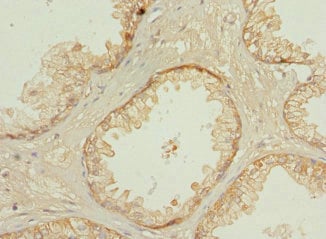

IHC (Immunohistochemisry)

(Immunohistochemistry of paraffin-embedded human prostate cancer using AAA232191 at dilution 1:100)